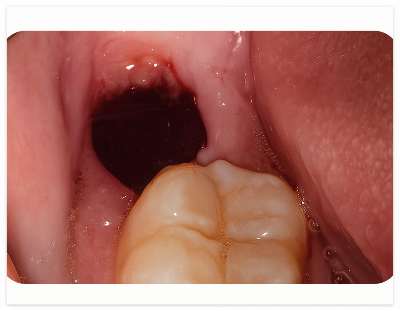

정상적으로 맹출 된 사랑니는

비교적 쉽게 뽑을 수 있지만

매복된 경우 잇몸을 절개하고

치아를 분리하여 발치해야 합니다.

이 경우 올바른 사랑니보다

출혈량이 많고 지혈도 더 오래 걸릴 수 있죠.